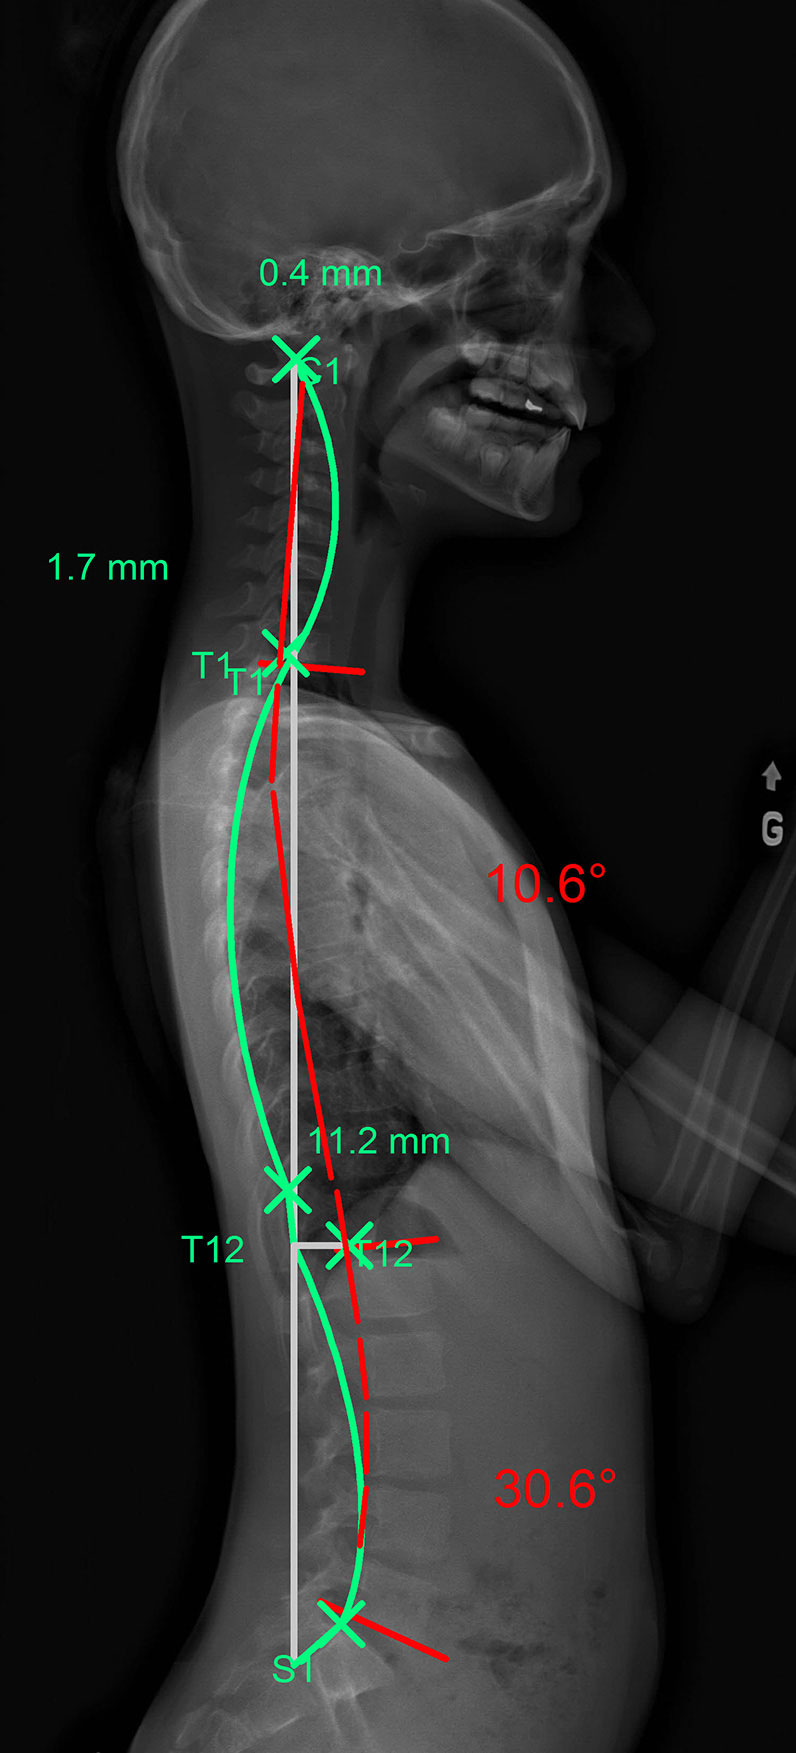

L’hypercyphose peut toucher de nombreuses parties de la colonne vertébrale thoracique. Sur les images suivantes, la ligne verte représente la courbe idéale que devrait avoir le patient. La ligne rouge représente, elle, la configuration anormale de sa cyphose.

La ligne verte représente la courbure idéale et la rouge celle que forme la colonne vertébrale du patient vue de profil.